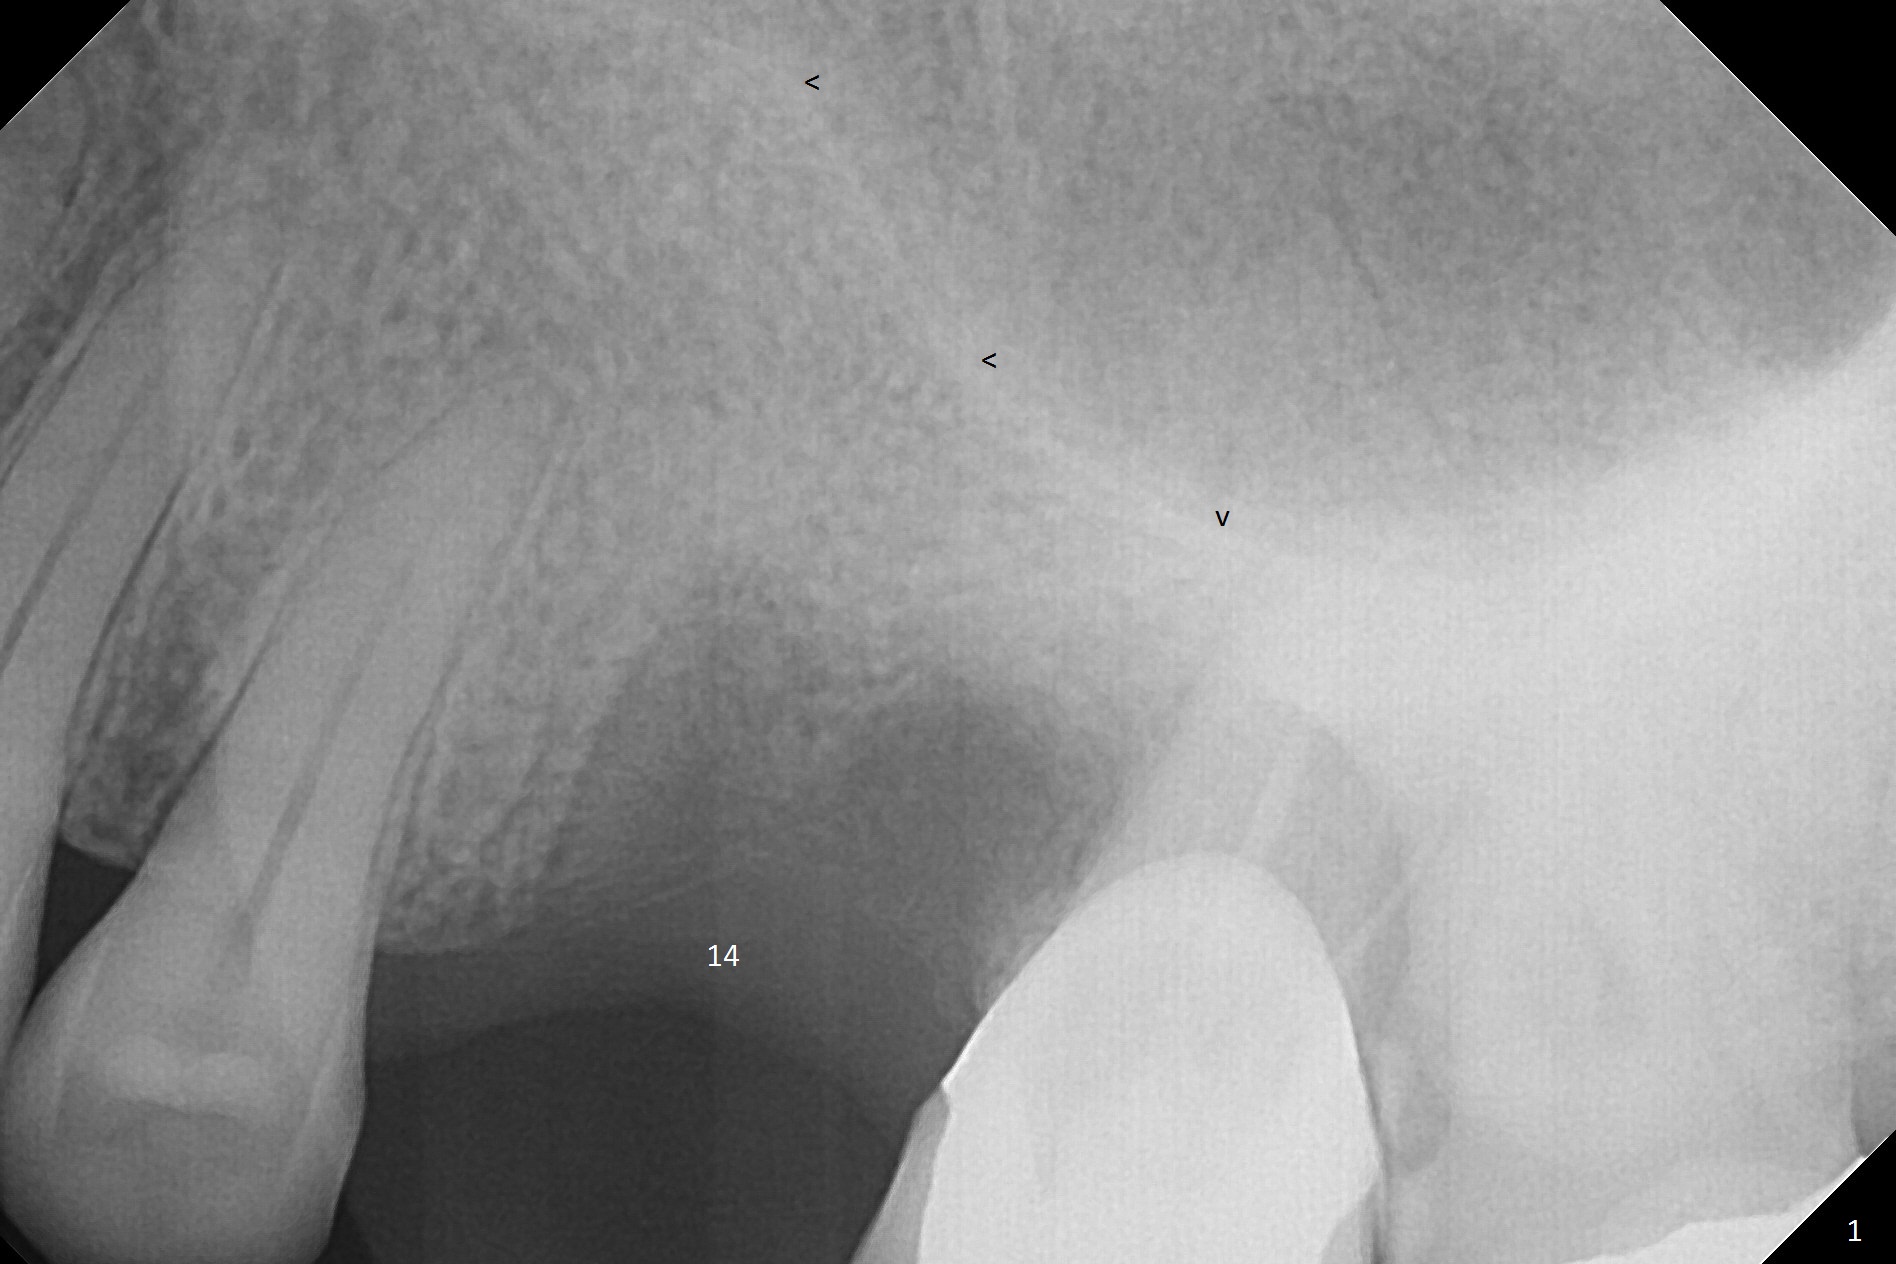

A 44-year-old woman will return to clinic for #14 implant placement 2.5 months post extraction (Fig.1).  The tooth used to have persistent fistula.  The bone density appears to be low coronally.  To compensate for the sloped sinus floor (arrowheads), start osteotomy as mesial as possible (Fig.2 red arrow) either with Magic Expander or Drill and place an implant as high as possible (Fig.3).  If there is buccal plate defect, place the implant as palatal and deep as possible.  Use Metronidazole routinely for sinus cases.